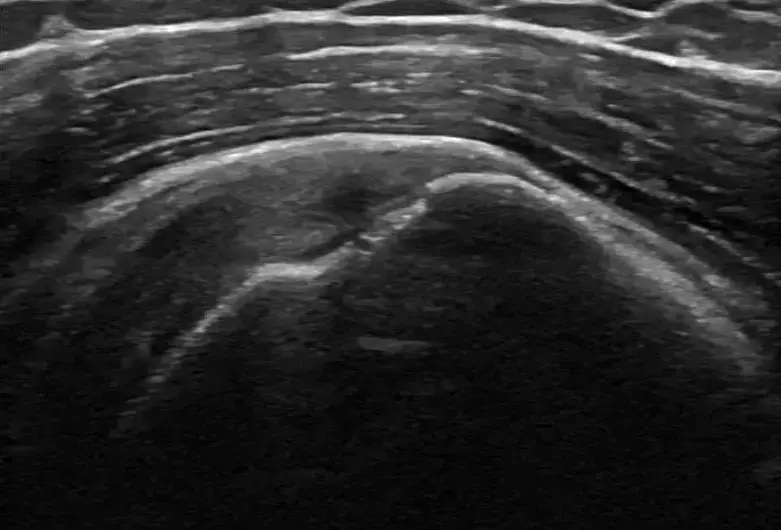

Located in Maui, Osteopathy on Maui, led by Dr. Brian Peternell D.O., is a dedicated osteopathic practice that blends traditional hands‑on manipulation with modern regenerative techniques. The clinic’s core identity centers on restoring the body’s innate healing capacity through precise, anatomy‑focused care for musculoskeletal conditions across the island. The team emphasizes a non‑surgical, evidence‑based approach, offering ultrasound‑guided PRP injections to accelerate tissue repair in tendons, ligaments, and joints. Complementary services such as osteopathic manipulation and cranial osteopathy support overall biomechanics, while targeted PRP therapy provides regenerative orthopedics for knee, hip, shoulder, hand, and ankle injuries. This philosophy prioritizes functional recovery and pain reduction without reliance on drugs or extensive surgery. Dr. Peternell brings board certification in Neuromusculoskeletal Medicine and Osteopathic Manipulative Medicine, backed by extensive training and a commitment to patient‑centered care. His expertise, combined with a supportive clinical environment, positions the practice as a trusted source for non‑surgical joint pain relief and regenerative medicine in Maui.